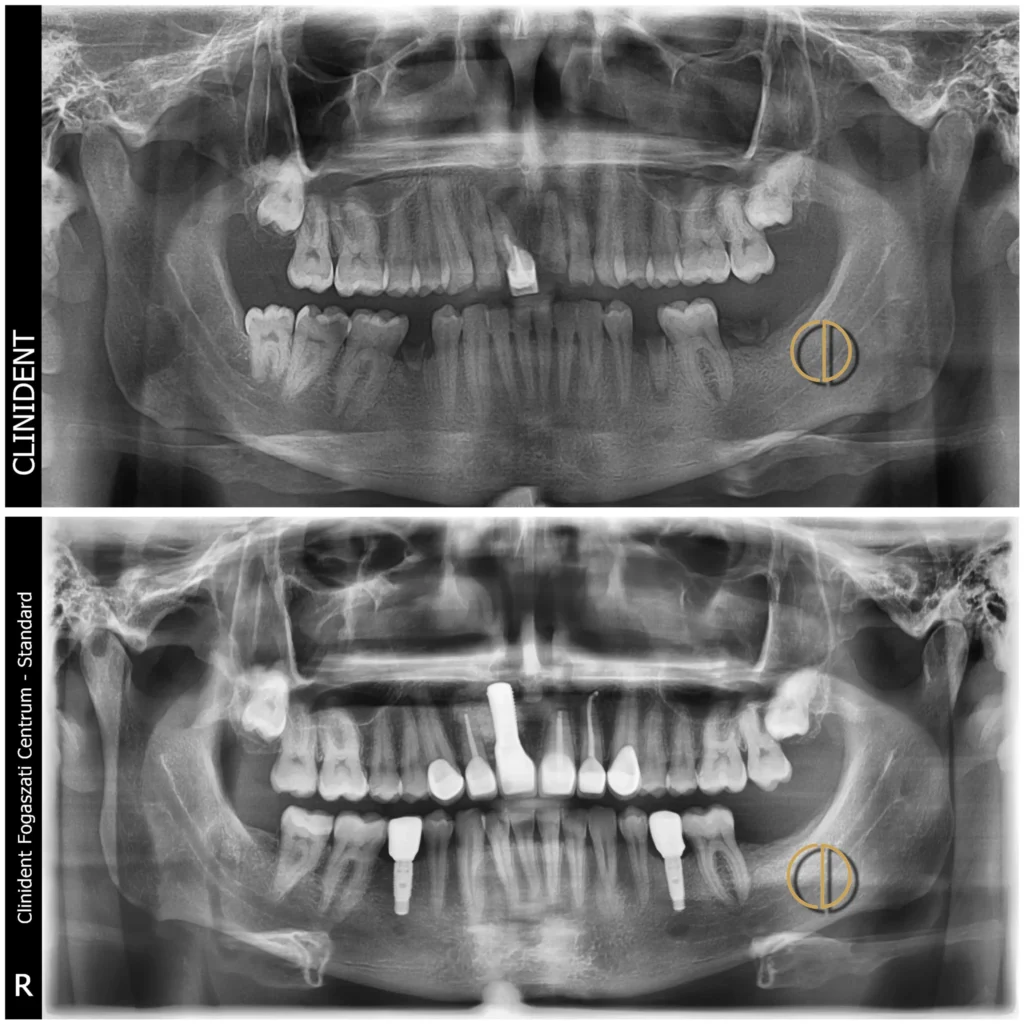

Negyvenes férfi páciensem letört fogak-, egy nagymetsző körüli gyulladásos tünetek és egyenetlen mosolykép miatt érkezett hozzám.

A fogászati CT-alapján végzett teljes állapotfelmérés alapján végül több frontfog körül gyulladás, illetve fogciszta volt megállapítható.

A letört fogak mellett a jobb felső nagymetsző is (11-es fog) menthetetlennek bizonyult, míg a két szomszédos fog (12, 21, 22) gyökérkezelésre szorult.

Az alsó foggyökér eltávolítással indult a rehabilitáció, amelyet a 12-es és 21-es fogak gyökérkezelése, majd csapos foggá alakítása követett.

A kezeléssorozat a fogciszta eltávolítással, a 12 és 21-es fogak rezekciójával, és a 11-es fog eltávolításával folytatódott, a műtét során csontpótlást is végzett a szájsebész. A mosolyzóna foghiányára azonnal ideiglenes fogpótlást készítettünk.

2. Implantáció

Az alsó rágófogak helyére titán implantátumok kerültek, míg a felső mosolyzónában a nagymetsző helyére Straumann kerámia implantátum került beültetésre.

Végül a mosolyzónába (13–23) 6 darab, az alsó implantátumokra pedig 1-1 darab cirkónium korona készült el, stabil, esztétikus és harmonikus eredményt adva.